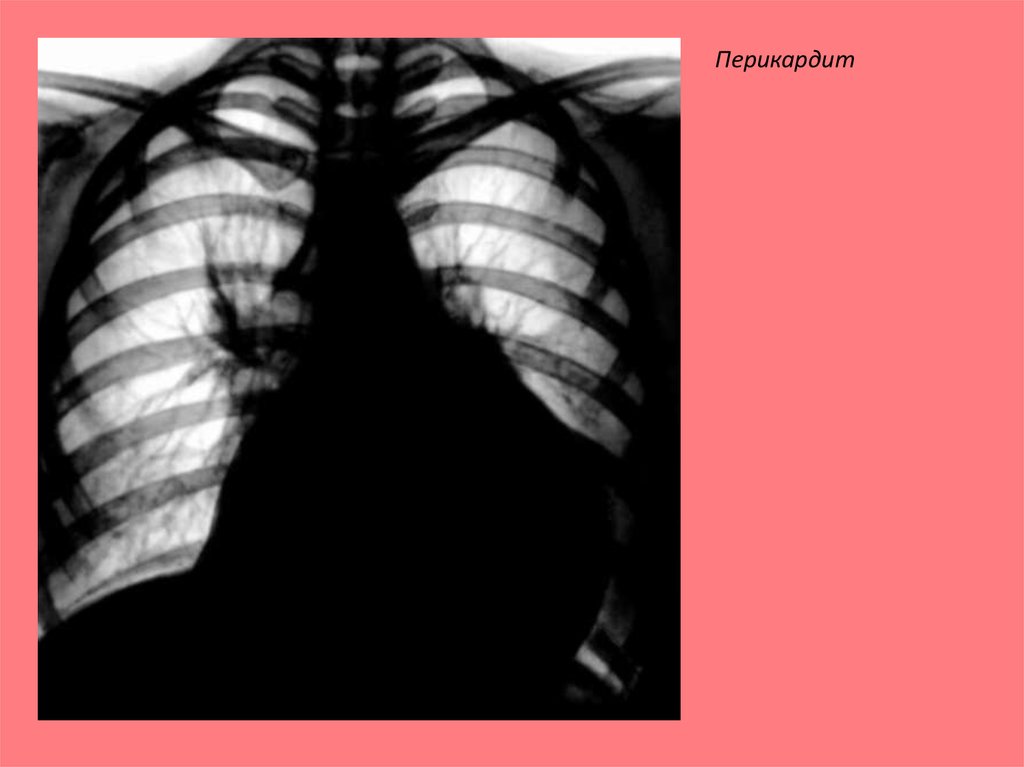

Перикардит